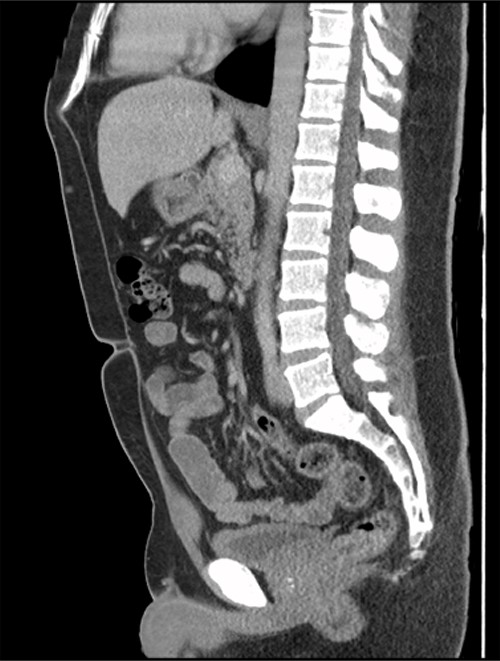

The patient had an uneventful recovery post operation. A retrospective review of the patient’s previous imaging revealed evidence of an appendicolith at the time of appendicitis diagnosis (Fig. 4). Despite the presence of the appendicolith on the preoperative CT, the histology of the resected appendix did not describe the presence of the imaged appendicolith. In addition, there was no evidence of a urachal lesion then on the initial imaging (Fig. 5), nor was there an intraoperative report of abdominal abnormalities during the appendicectomy. Therefore, it is hypothesized that the urachal lesion was an abscess secondary to the retained appendicolith from the appendicectomy.

Sagittal CT image. No obvious abnormalities at the dome of the bladder.